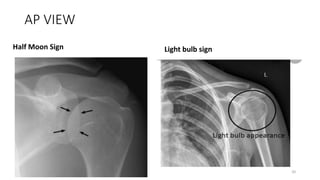

AP VIEW

Half Moon Sign Light bulb sign